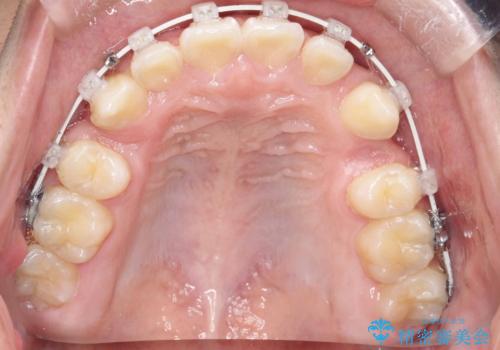

八重歯・歯並びのデコボコとディープバイトを改善した抜歯ワイヤー矯正症例

- ワイヤー(審美装置)

矯正の精密検査の結果上顎左右4番の計2本を抜歯し、審美性に配慮したワイヤー矯正装置(審美装置)を用いて治療を行いました。

八重歯などの歯列のデコボコが綺麗に改善され、患者様にも大変喜んでいただけました。また、咬み合わせが深い「ディープバイト」も併せて改善し、見た目だけでなく機能面でもバランスの取れた咬合を獲得しています。